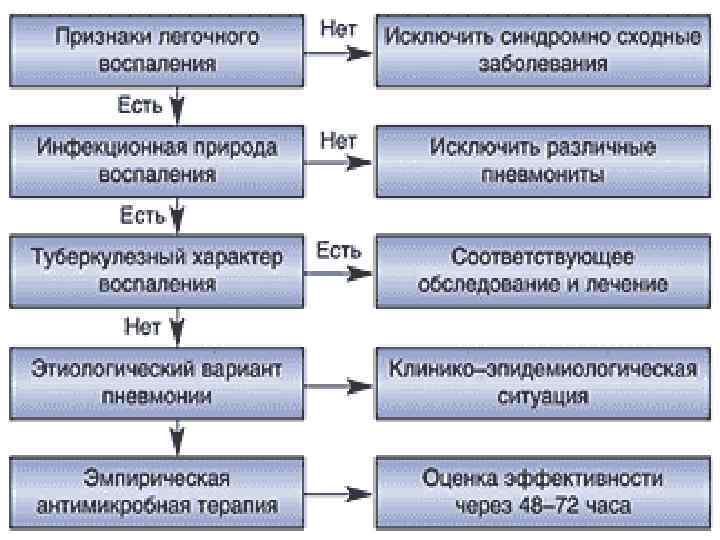

При проведении дифференциального диагноза пневмонии следует исключить другие заболевания, сопровождающиеся притуплением перкуторного звука при сравнительной перкуссии лёгких, кашлем и болями грудной клетки: острый бронхит, туберкулёз и рак лёгкого.

Анализируя весь симптомокомплекс у больного, то есть жалобы на постоянные, интенсивные, колющие боли в правой половине грудной клетки, усиливающиеся при дыхании, пальпации и кашле, кашель с выделением слизистой мокроты, слабость, одышку смешанного характера и повышение температуры тела; данные из анамнеза заболевания: резкое развитие всех симптомов, высокая лихорадка (39(С), появления слабости; данные объективного исследования: уменьшение подвижности нижнего края правого легкого, притупление перкуторного звука справа в нижнем отделе, появление жёсткого дыхания и наличие влажных мелкопузырчатых хрипов; данные лабораторно-инструментальных исследований: наличие в крови лейкоцитоза(15, 3*10(9/л) с преобладанием в лейкоцитарной формуле палочкоядерных, при рентгенологическом исследовании грудной клетки обнаружение инфильтрации в нижней доле правого легкого,

Мы можем выделить несколько главных синдромов: болевого, интоксикационного, дыхательной недостаточности.

Данные объективного и лабораторноинструментального исследований позволяют связать эти синдромы с поражением нижнего отдела правого легкого, характерного для пневмонии.

Окончательный диагноз будет звучать: Внебольничная правосторонняя очаговая нижнедолевая пневмония, средней степени тяжести. ДН 0.